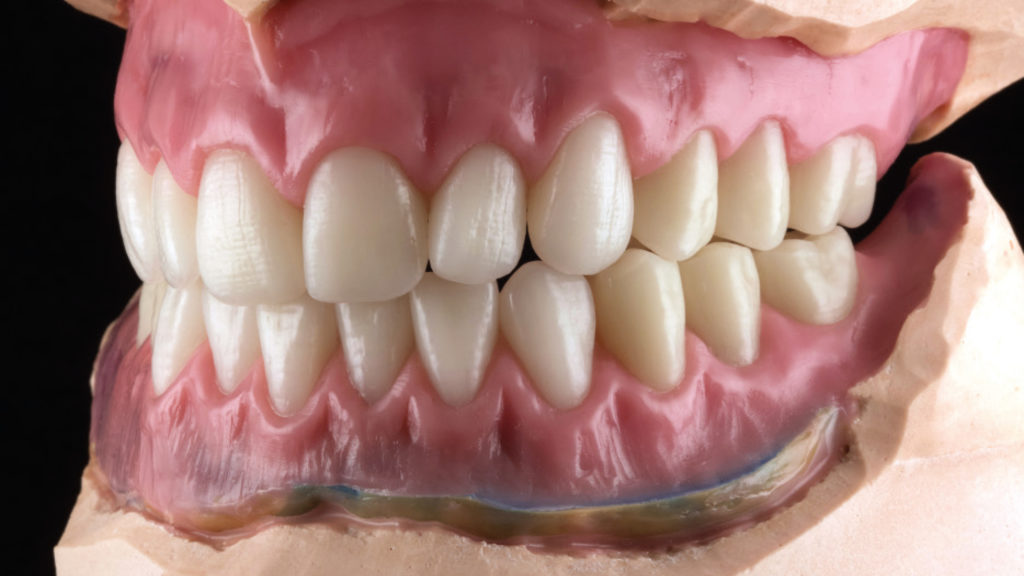

Die Aufstellung mit dieser Frontzahngarnitur ging daher intuitiv und zügig von der Hand (Abb. 5 bis 7). Die breiten Palatinalleisten unterstützen zusätzlich die Ausgestaltung der Papillen. Bei neuen Rehabilitationen muss immer berücksichtigt werden, wie das Gebiss des Patienten vorher ausgesehen hat. Die Basis ist die Anatomie der Mundhöhle am Tag des Behandlungsbeginns, die ich beginne nach den Parametern Ästhetik, Funktion und Stabilität zu versorgen. Alle klinischen Informationen müssen dabei berücksichtigt werden, um die besten Rehabilitationsergebnisse im Mund des Patienten zu erzielen. Aufgrund der Position und der Mesialwanderung von Zahn 46 war der Platz für die untere Frontzahnaufstellung reduziert und wurde verschachtelt realisiert, um physiologische Molarenkontakte zwischen den Konfektionszähnen herstellen zu können.

Die Patientin war einverstanden, da ihre natürlichen Frontzähne im Unterkiefer ebenfalls verschachtelt gewesen und nie mit einer kieferorthopädischen Behandlung nivelliert worden waren. Eine effiziente Aufstellung mit exakt definierter Zentrik, aber der nötigen Freiheit bei exzentrischen Bewegungen, gewährleistet der Vitapan Lingoform im Seitenzahnbereich. Sein multifunktionelles Kauflächendesign nach dem Zahnradprinzip ist universell für alle gängigen Aufstellkonzepte in Zahn-zu-Zahn oder Zahn-zu-zwei-Zahn geeignet.